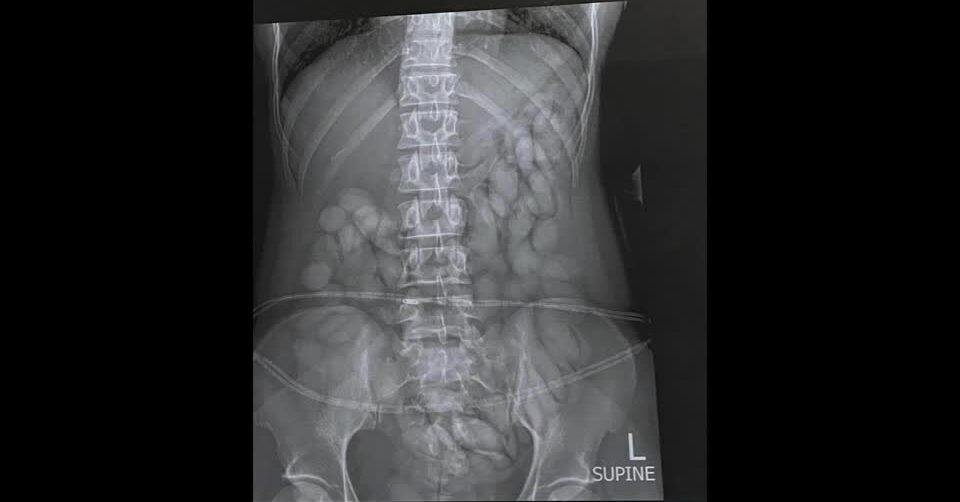

ตำรวจแอฟริกาใต้จับกุมผู้ต้องสงสัยรายหนึ่งที่สนามบินโออาร์ แทมโบ ในนครโจฮันเนสเบิร์กเมื่อวันอาทิตย์ตามเวลาท้องถิ่น หลังได้รับเบาะแสจากหน่วยข่าวกรองว่า จะมีคนนำยาเสพติดเข้าประเทศ ผู้ต้องสงสัยเป็นสตรีชาวนามิเบียวัย 30 ปีเดินทางมาจากนครเซาเปาลูของบราซิล ผลการตรวจค้นร่างกายไม่พบสิ่งผิดกฎหมาย ตำรวจจึงนำตัวไปเข้าเครื่องตรวจเอ็กซเรย์ และพบบรรจุภัณฑ์มีลักษณะคล้ายแคปซูลขนาดใหญ่รูปร่างเหมือนกระสุนอยู่เต็มกระเพาะอาหาร สันนิษฐานว่าภายในบรรจุโคเคน

ตำรวจนำตัวผู้ต้องสงสัยไปโรงพยาบาลเพื่อหาทางนำแคปซูลเหล่านั้นออกจากร่างกาย ล่าสุดนำออกมาได้แล้ว 63 แคปซูล โดยภาพของกลางที่ตำรวจนำมาโชว์นั้นเป็นแค่เพียงบางส่วนเท่านั้น และขณะนี้ยังนำออกมาจากท้องของผู้ต้องสงสัยไม่หมด ทำให้ตำรวจยังไม่สามารถประเมินราคาของยาเสพติดดังกล่าวได้.-816(814).-สำนักข่าวไทย